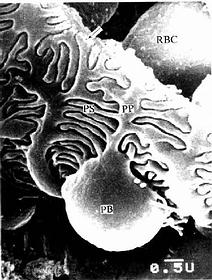

(2)肾小囊(renal capsule)又称Bowman囊,是肾小管起始部膨大凹陷而成的双层囊,似杯状,囊内有血管球(图15-3,15-4)。肾小囊外层(或称肾小囊壁层)为单层扁平上皮,在肾小体的尿极处与近端小管上皮相连续,在血管极处反折为肾小囊内层(或称肾小囊脏层),两层上皮之间的狭窄腔隙称肾小囊腔,与近曲小管腔相通。内层细有胞形态特殊,有许多大小不等的突起,称为足细胞(podocyte)(图15-5,15-6)。足细胞体积较大,胞体凸向肾小囊腔,核染色较浅,胞质内有丰富的细胞器,在扫描电镜下,可见从胞体伸出几个大的初级突起,继而再分成许多指状的次级突起,相邻的次级突起相互穿插成指状相嵌,形成栅栏状,紧贴在毛细血管基膜外面(图15-7)。突起之间有直径约25nm的裂隙,称裂孔(slit pore),孔上覆盖一层厚4-6nm的裂孔膜(slit membrane)(图15-5)。突起内含较多微丝,微丝收缩可使突起活动而改变裂孔的宽度。足细胞表面也覆有一层富含唾液酸的糖蛋白。

图15-7 兔肾小体扫描电镜像 示足细胞

PB足细胞体,PP初级突起,PS次级突起,RBC红细胞,

↑基膜(河北医学院电镜供图)